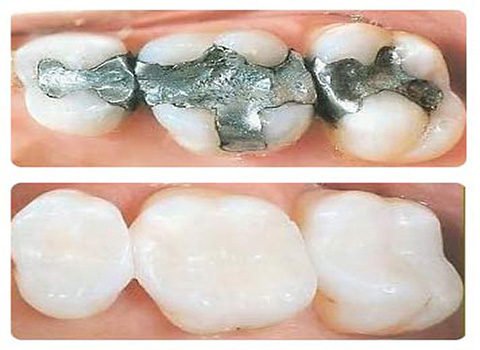

Namman Dental hospital all of your dental needs under one roof and that includes specialists, flexibility in scheduling, inexpensive treatments and much more.